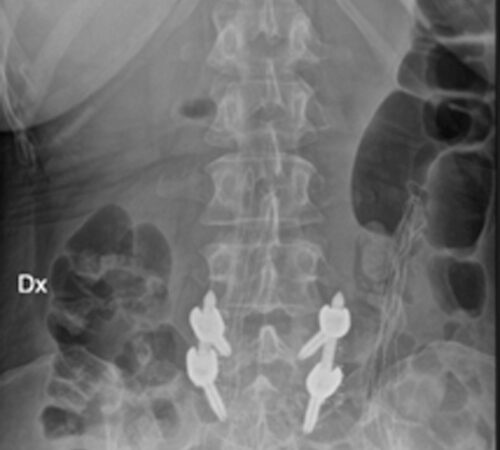

DIAGNOSI:

SPONDILOLISTESI CON STENOINSTABILITA’ L3-L5

Radiografia lombare pre-operatoria

Intervento chirurgico eseguito:

Artrodesi lombare mediante viti transpeducolari L3-L4-L5 + introduzione di cage intersomatica plif

Radiografia post-operatoria